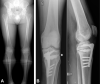

Results: A total of 69 consecutive patients were analyzed, of whom 38 underwent OWHTO and 31 underwent DLO surgery. A significant between-group difference was found for all radiological parameters; in particular, there was less joint line obliquity after DLO compared with OWHTO (1.7° vs 5.6°; P < .001). DLO provided better outcomes compared with OWHTO regarding the UCLA score (4.3 vs 6.7; P < .001) and patient satisfaction (2.6 vs 3.9; P < .001), but no significant difference in KOOS or return to work or sports was observed. The OWHTO group had more hinge fractures than the DLO group (34.2% vs 12.9%; P < .001).

Conclusion: For combined tibial and femoral varus deformity, DLO produced more physiologic joint line obliquity with slightly improved UCLA and patient satisfaction scores. A greater incidence of hinge fracture was observed after isolated OWHTO compared with DLO due to a larger tibial correction; however, this had little effect on clinical results at the 2-year follow-up.